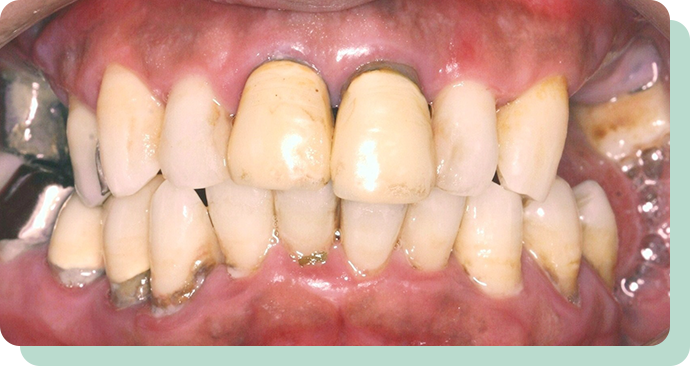

処置前後

左の写真は、歯周病が進んで、どんどん歯が抜けていっている状態です。

この方は、歯を短くし、金属のキャップの上に特殊な入れ歯を装着。

これにより、快適にお食事ができるようになりました。